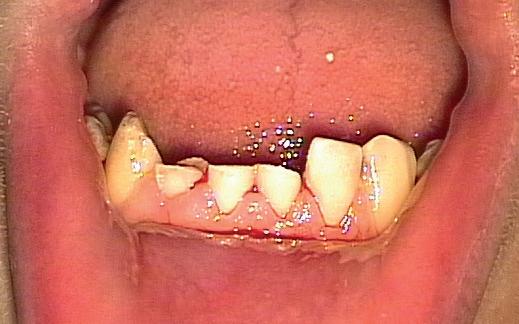

Bij een 15-jarige gezonde jongen werd tijdens een caféruzie op zondagnacht een stoel tegen zijn gezicht gegooid. Hierbij was sprake van flink dentaal trauma:

• De 13 was geavulseerd.

• De 12 en de 11 waren naar palatinaal geluxeerd.

• In het onderfront waren kroonfracturen zichtbaar in de 42, 41 en 31.

Na de avulsie is de 13 bij de afdeling kaakchirurgie in een oplossing van fysiologisch zout bewaard (onbekend hoe lang na het trauma) en na ongeveer zes uur post-trauma onder anesthesie in de alveole teruggeplaatst. Toen zijn ook de 12 en de 11 gereponeerd en is er een staaldraadspalk aangebracht van de 14 naar de 22. Tevens is de lip gehecht. Er is niets aan de afgebroken ondertanden gedaan, maar dringend geadviseerd deze zo snel mogelijk te laten afdekken door de eigen tandarts.

Na zes weken zagen wij hem voor het eerst bij ons in de praktijk voor consult. Hij was klachtenvrij en kon redelijk kauwen met zijn tanden (afbeelding 1-6).